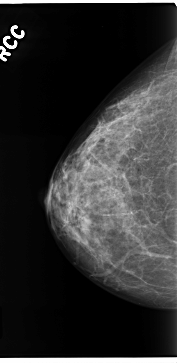

C_0206_1.RIGHT_CC

RIGHT_CC LINES 4712 PIXELS_PER_LINE 2296 BITS_PER_PIXEL 12 RESOLUTION 50 NON_OVERLAY